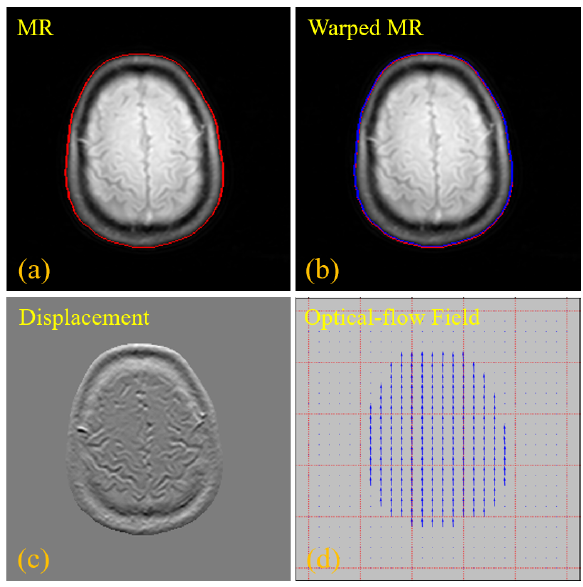

Small Methods | 一种用于归档和检索医学磁共振成像数据的高效DNA存储系统

近日,中国科学院深圳先进技术研究院姜青山研究员、黄小罗高级工程师、中国农业科学院深圳农业基因组研究所戴俊彪研究员等联合设计了一种名为"EDS"的DNA存储方法,通过改进编码模型、引入冗余核苷酸和设计索引技术,实现了医学MRI数据的可靠归档和检索。

近日,中国科学院深圳先进技术研究院姜青山研究员、黄小罗高级工程师、中国农业科学院深圳农业基因组研究所戴俊彪研究员等联合在国际学术期刊Small Methods (IF=12.4)上发表了题为An Effective DNA-Based File Storage System for Practical Archiving and Retrieval of Medical MRI Data...